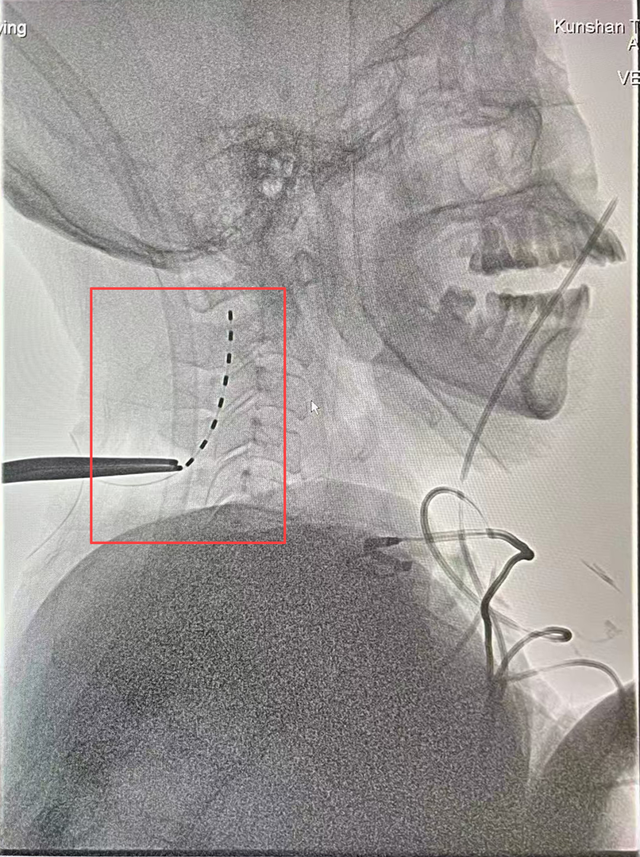

▲神经外科团队为张女士行临时脊髓电刺激术(ST-SCS)

几周后,神经外科陈龙主任医师与陆维主治医师在王文华主任的指导下,为张女士实施临时脊髓电刺激术(ST-SCS)。

术中,电极被精准植入颈髓C2-C4水平硬膜外,通过脉冲刺激激活上行网状系统,促进脑皮层代谢与电活动。